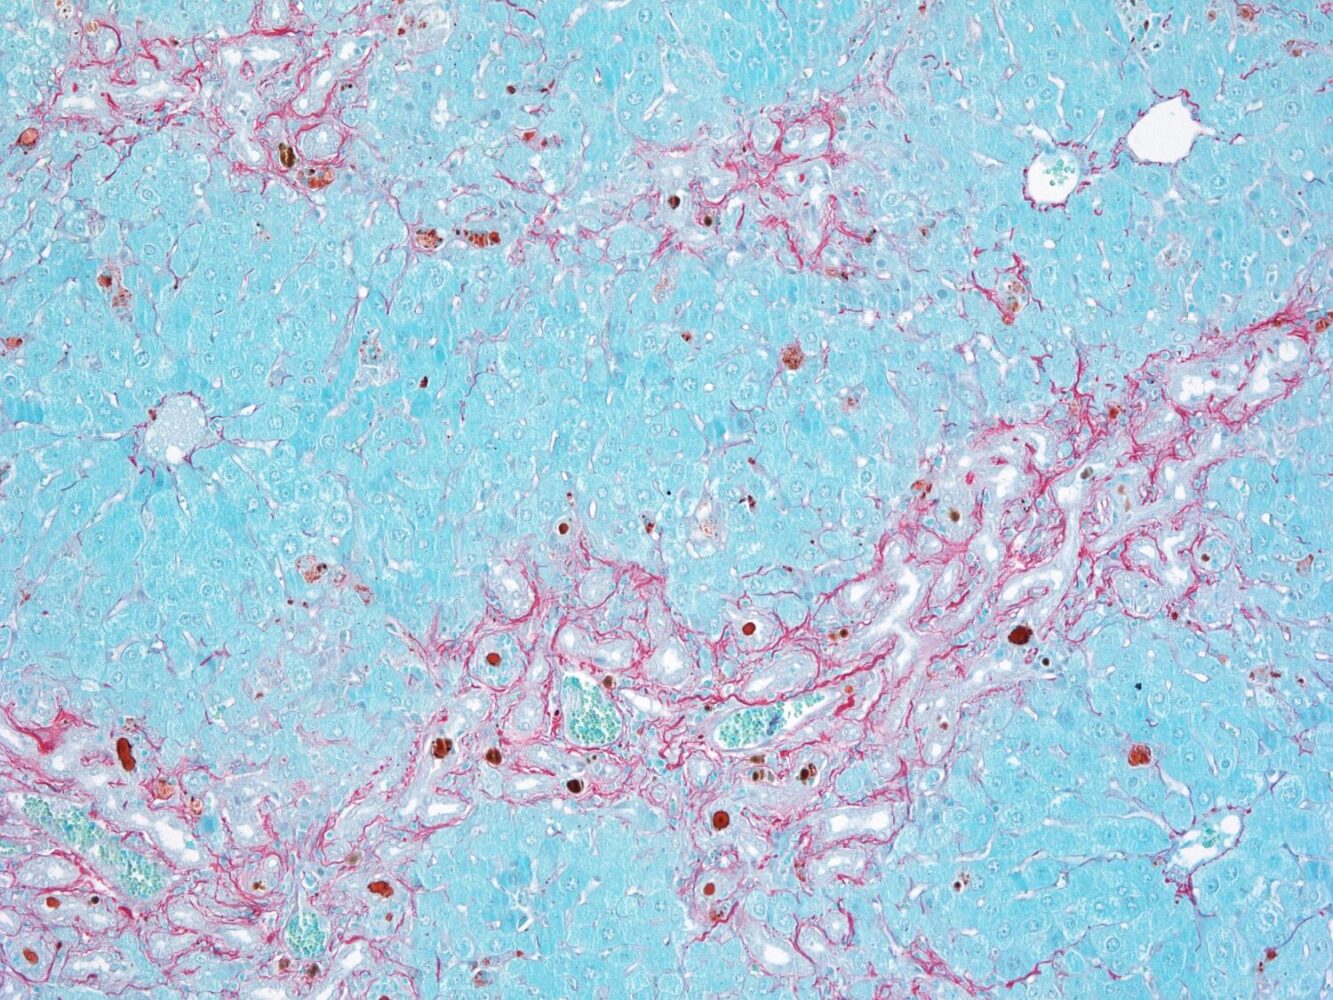

Muchas enfermedades del hígado comparten una característica común: la fibrosis, es decir, la acumulación progresiva de cicatrices en el tejido hepático. Esas cicatrices, que surgen como respuesta del hígado a lesiones o agresiones persistentes, pueden impedir al órgano funcionar correctamente. La fibrosis afecta a millones de personas en todo el mundo y constituye un paso decisivo en la progresión hacia la cirrosis, una patología potencialmente letal que puede evolucionar hacia cáncer de hígado.

El nuevo estudio del CNIO ha identificado el mecanismo molecular que ayuda a los conductos biliares a evitar la fibrosis. En condiciones normales, las células BEC expresan en su interior una proteína, el receptor FXR. Cuando la bilis circula por los conductos biliares, FXR detecta los ácidos biliares, se une a ellos y activa la producción de otra proteína llamada YAP. Se forman entonces unas moléculas de adhesión que mantienen las células BEC tan pegadas entre sí, que la bilis no tiene acceso al tejido hepático. Al mismo tiempo, YAP limita la proliferación excesiva de células BEC, ya que regula la activación de una tercera proteína esencial para su multiplicación.

Este sistema es clave para que los conductos biliares funcionen como una barrera eficaz. Sin embargo, en algunas enfermedades o condiciones genéticas, la proteína FXR deja de funcionar correctamente o de expresarse, y las células BEC pierden este mecanismo de control: proliferan en exceso, la barrera se debilita y se producen fugas de los ácidos biliares hasta el tejido que realiza las funciones del hígado –el parénquima hepático–.

Al llegar a zonas del hígado donde no deberían estar, los ácidos biliares activan otras células –las células estrelladas–, que generan cicatrices. Si estas se acumulan, dan lugar a la fibrosis hepática. Tanto la proliferación excesiva de las células BEC como la fibrosis pueden progresar hacia cirrosis hepática, una enfermedad grave y potencialmente mortal.